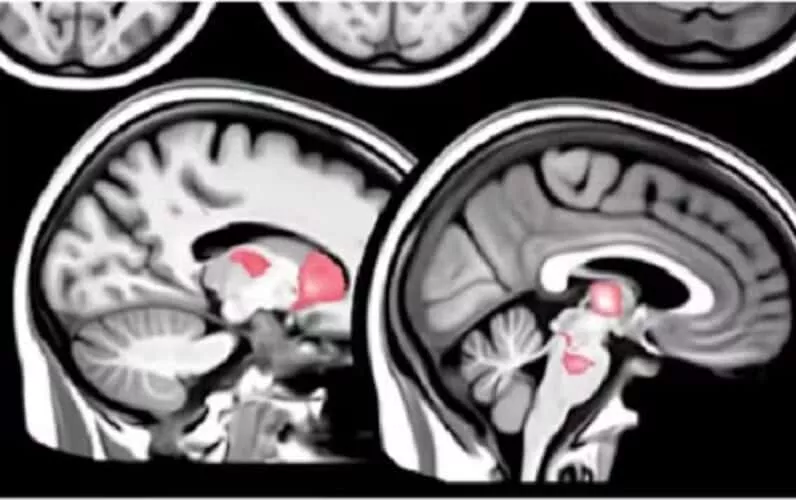

Nova študija razkriva, da "cepiva" mRNA povzročajo nenormalne imunske odzive, ki vodijo do dolgotrajne poškodbe možganov.